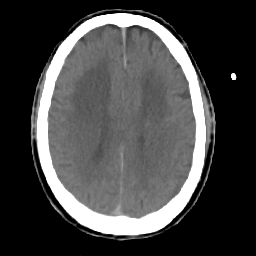

Meningioma: Roentgen-ray CT #2 -- Slice #13

[Home][Help][Clinical] Slice 13